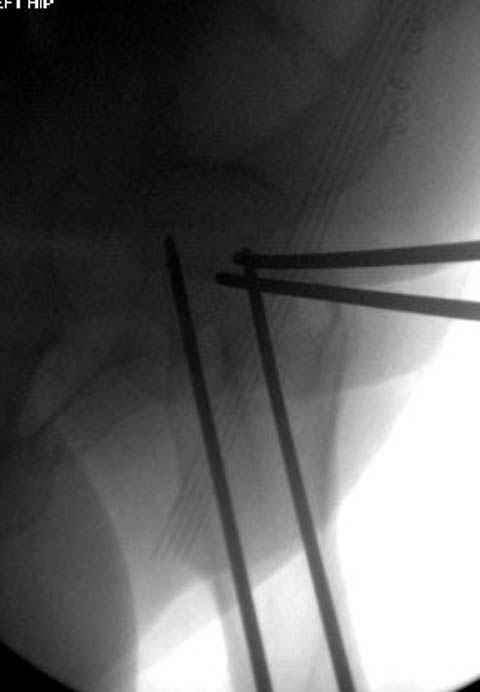

Фиксацию шейки провели когда получили окно, быстро

перкутанно смогли провести шурупы.

Перелом шейки смогли зафиксировать через пару дней, ацетабулум до сих пор не оперирован, на вытяжении.